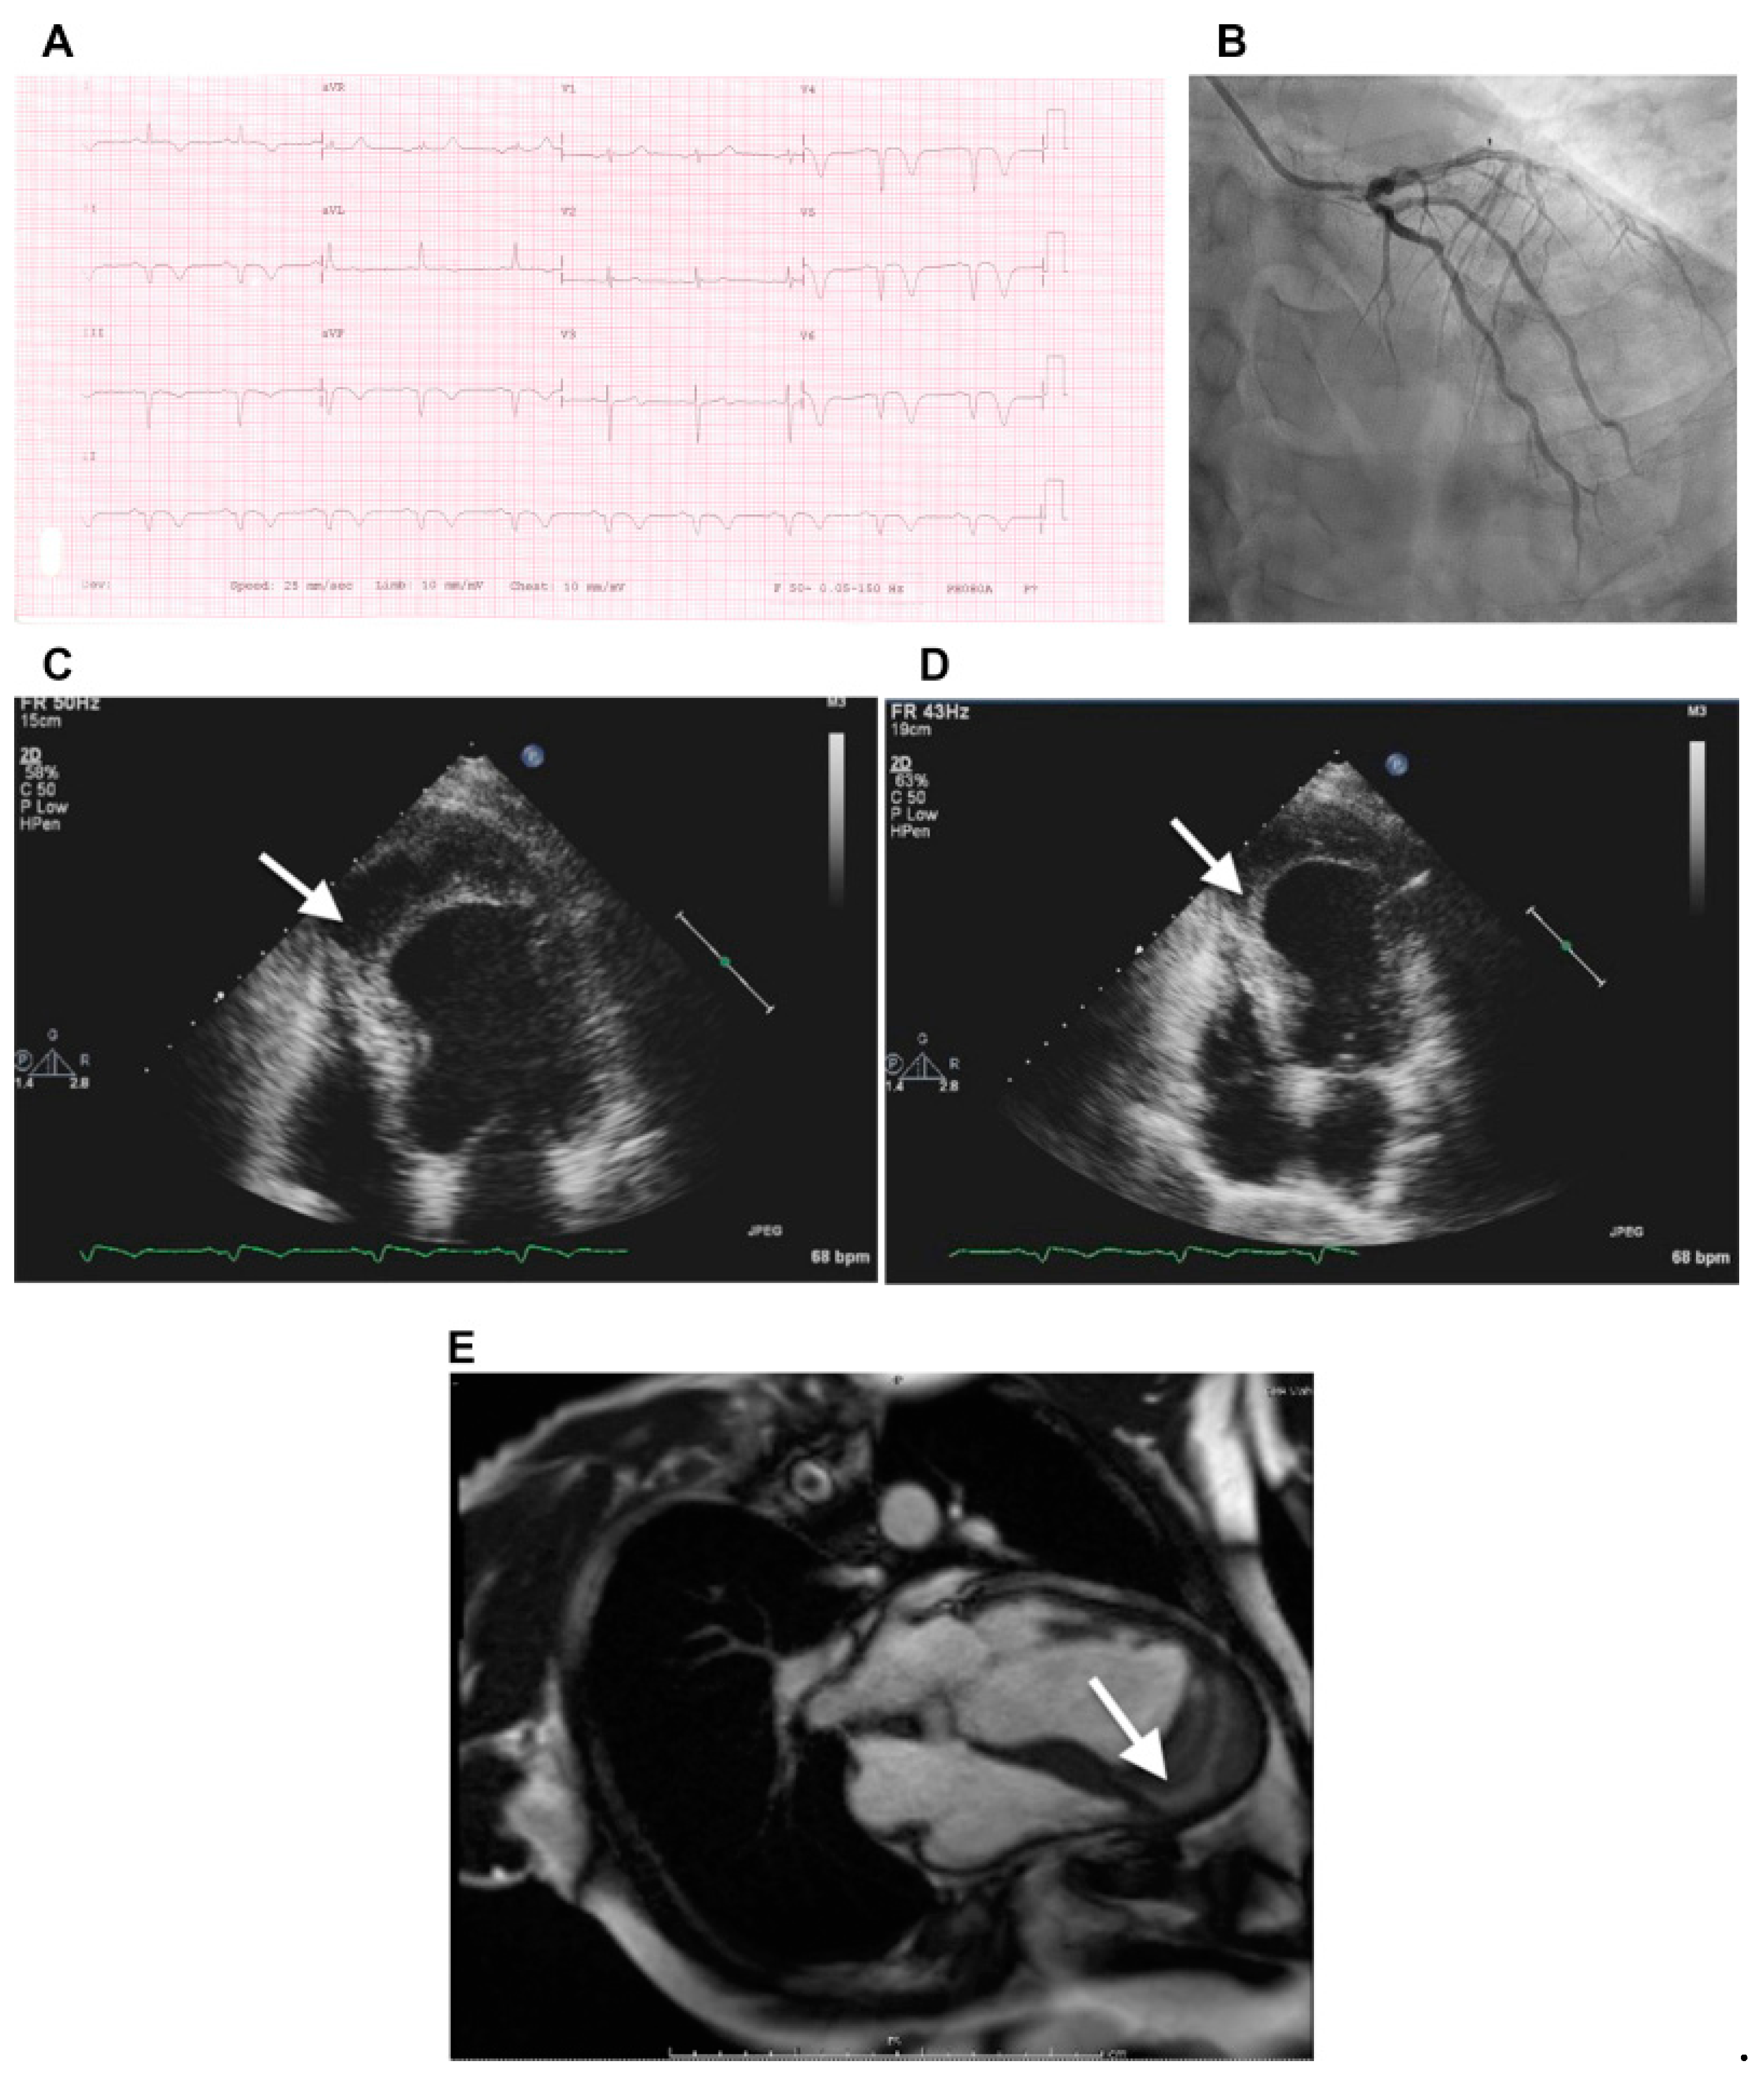

4.4. Septal Infarction

- Jones, B.M.; Kapadia, S.R.; Smedira, N.G.; Robich, M.; Tuzcu, E.M.; Menon, V.; Krishnaswamy, A. Ventricular septal rupture complicating acute myocardial infarction: A contemporary review. Eur. Heart J. 2014, 35, 2060–2068. [Google Scholar] [CrossRef] [Green Version]

- Roslan, A.; Jauhari Aktifanus, A.T.; Hakim, N.; Megat Samsudin, W.N.; Khairuddin, A. Intramyocardial Dissecting Hematoma in Patients with Ischemic Cardiomyopathy: Role of Multimodality Imaging in Three Patients Treated Conservatively. Case 2017, 1, 159–162. [Google Scholar] [CrossRef] [PubMed] [Green Version]